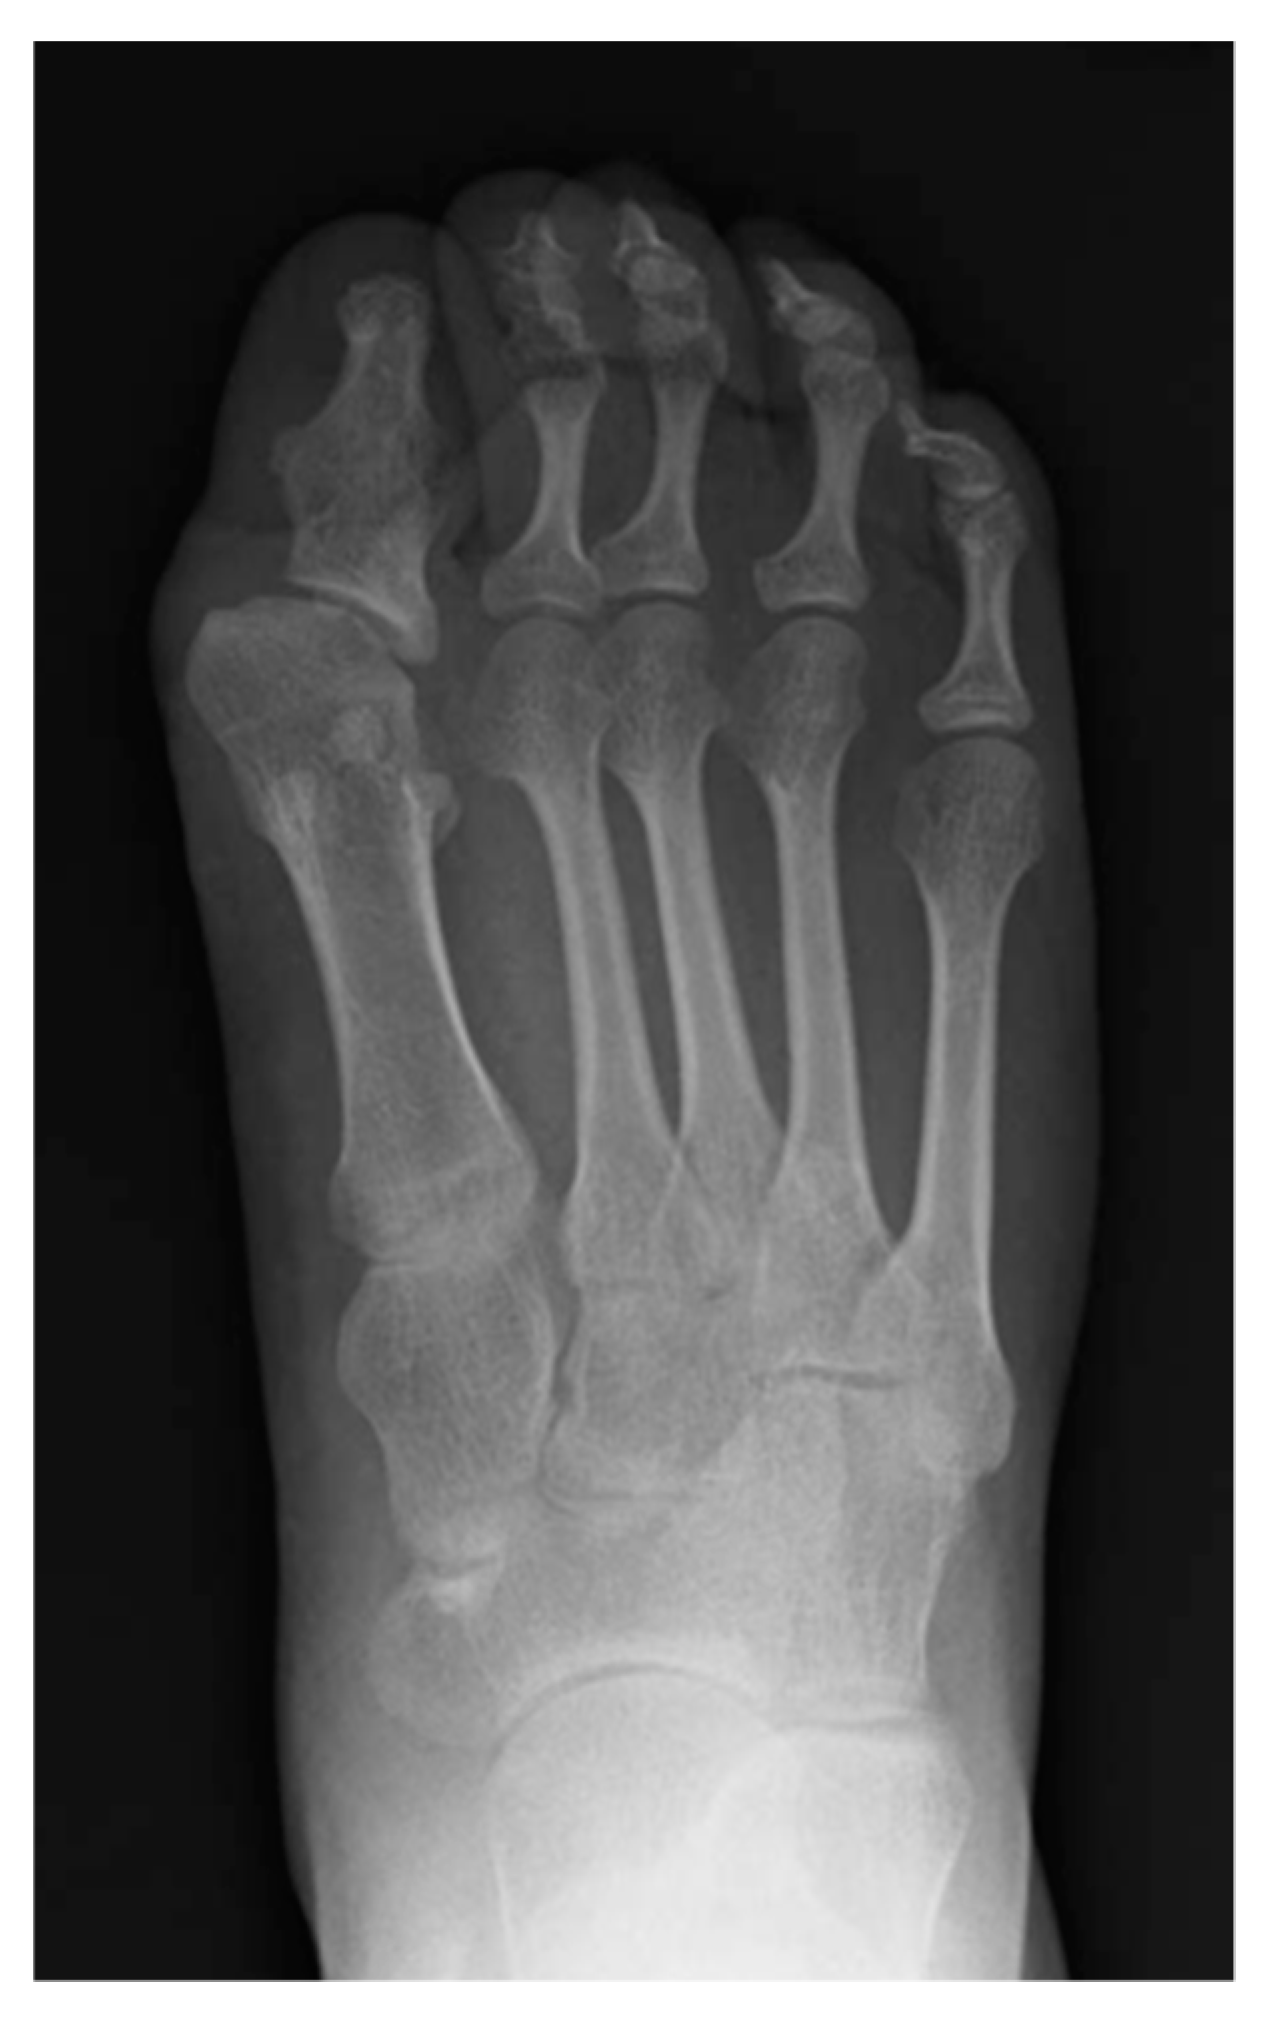

- Mishima, K.; Kitoh, H.; Haag, N.; Nakashima, Y.; Kamizono, J.; Katagiri, T.; Susami, T.; Matsushita, M.; Ishiguro, N. Radiographic characteristics of the hand and cervical spine in fibrodysplasia ossificans progressive. Intractable Rare Dis. Res. 2014, 3, 46–51. [Google Scholar] [CrossRef]

- Nakashima, Y.; Haga, N.; Kitoh, H.; Kamizono, J.; Tozawa, K.; Katagiri, T.; Susami, T.; Fukushi, J.; Iwamoto, Y. Deformity of the great toe in fibrodysplasia ossificans progressive. J. Orthop. Sci. 2010, 15, 804–809. [Google Scholar] [CrossRef] [PubMed]